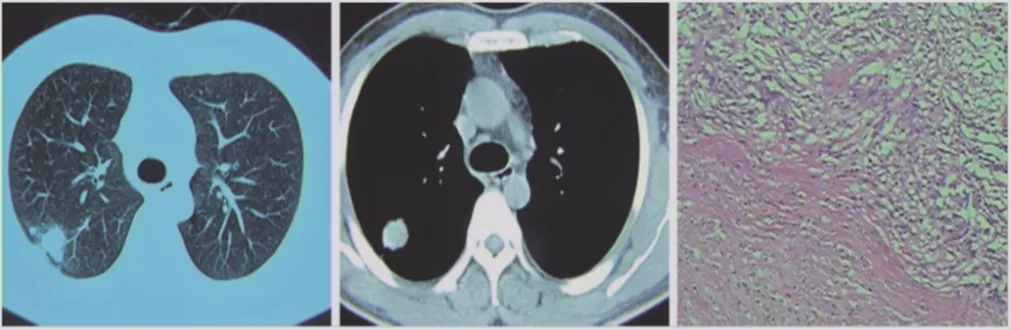

小细胞肺癌

小细胞肺癌以中央型多见,但是也有少数为周围型病灶。多为单个实性结节或肿块,可见分叶、毛刺、血管集束征、胸膜牵拉征。实际上我们很难从影像学上判断出小细胞肺癌的病理类型,往往是活检或者手术以后才能证实。如下图示,这属于I期的小细胞肺癌,进行手术的效果非常好。所以对于周围型小细胞肺癌,如果在结节很小的时候判断出来就做了手术,疗效非常好。我们知道小细胞肺癌是肺癌中治疗效果最差的,恶性程度是最高的。如果早期手术,仍然能够起到很好的效果。